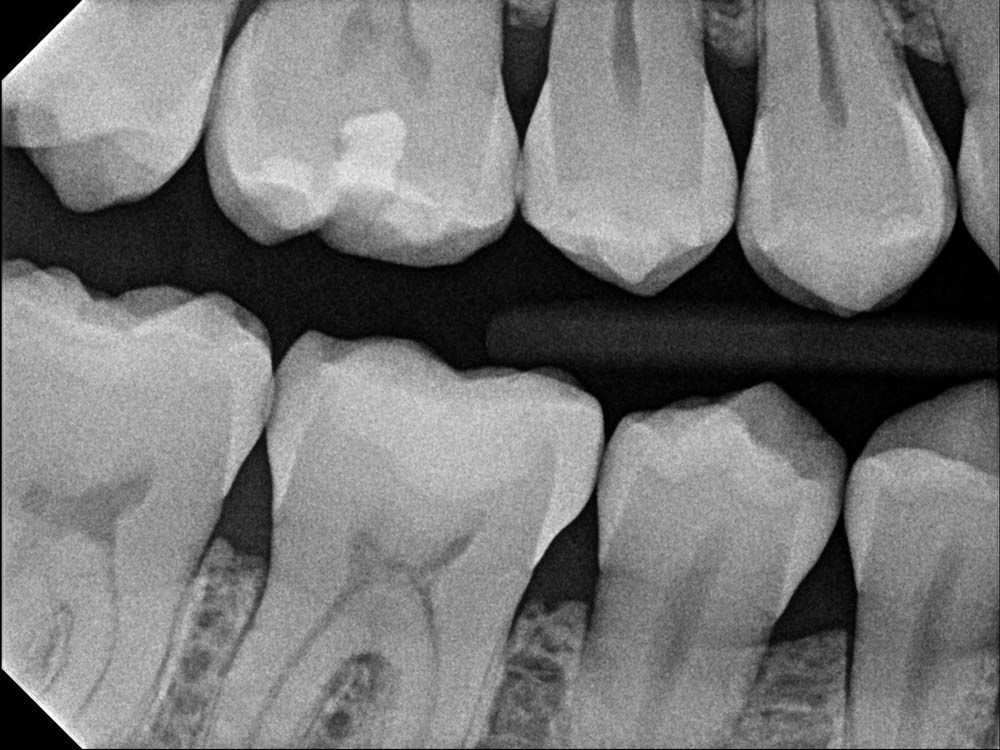

Bitewing X-Ray (BTW X-Ray)

Another common type is the bitewing X-Ray (BTW). Bitewings show portions of the teeth above the gums of the upper and lower teeth in a specific area. This view is great for detecting decay that is not visible during a visual exam. Bitewings also show the level of the bone supporting the teeth which helps us diagnose early stages of periodontal disease. A set of bitewings usually includes a view of the premolar and molar areas on both sides of the mouth.

Cavities (Dental Caries): Bite-wing and PA images are great at detecting dental decay in the areas hard to see visually. Early detection means minimally invasive treatments to prevent further damage.

Evaluation of Restorations: Bite-wing and dental PA are used to check the fit and integrity of existing restorations, like porcelain or composite fillings, dental crowns and bridges, to make sure they are sealed and not causing further problems.